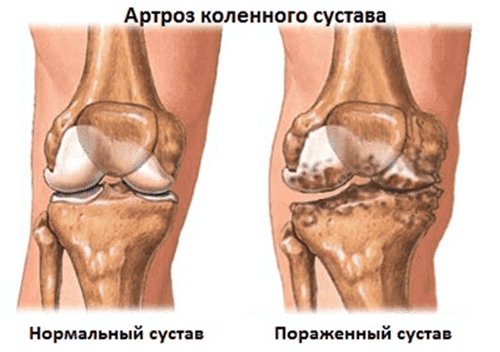

Ҳаракатсиз турмуш тарзи, стресс, овқатда кўп миқдорда туз ва шакар - буларнинг барчаси пай тўқималарни юмшатади, эскиртиради ва ингичкалаштиради. Ҳар бир янги ҳаракатдан пай ишқаланади ва деформацияланади, суяклар бир-бирига том маънода "қиришни" бошлайди, бу еса оғриқли зарбани келтириб чиқаради.

Статистик маълумотлар шундан иборатки, 35 ёшдан ошган одамларнинг 45% дан ортиғи бўғим касалликларга эга! Ҳаммаси аста-секин бошланади: улар қаердадир ҳаддан ташқари қаттиқ ҳаракат қилишади, қаердадир оғир юк кўтаришади, қаердадир шунчаки бўйнини шамоллатишади. Бўғим шундай яратилганки, асосий муаммолар бўғим суюқлигининг яллиғланиши билан бошланади, сўнгра пай юмшашни бошлайди ва натижада - ногиронлик пайдо бўлади.

Бўғим касаллиги тез ривожланади.

Буларнинг барчасида ёдда тутиш керак бўлган муҳим нарса шундаки, бўғимдаги касалликлар сизни 3 йилдан камроқ вақт ичида ногиронлар аравачасига ўтқазади!

Касаллик шундай ривожланади:

Бўғим суюқлигининг яллиғланиши - пай юмшаши ва унинг ингичкалаши - ўткир оғриқ

синдроми - ҳаракат қилиш қобилиятини йўқотишга олиб келади.